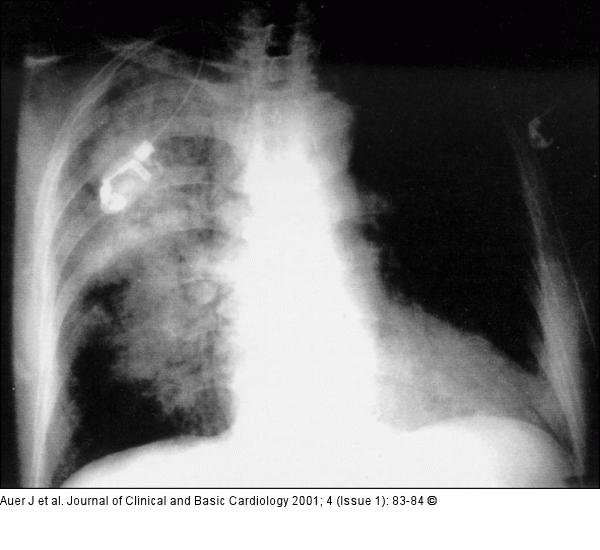

Figure/Graphic 2: Lungeninfiltrat Posterior-anterior chest radiograph ten hours after stenting and abciximab bolus showed a patchy infiltrate in the right lung |

Posterior-anterior chest radiograph ten hours after stenting and abciximab bolus showed a patchy infiltrate in the right lung |